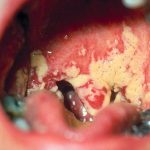

Незаметно присутствуя в организме, грибок вызывает кандидоз горла (фото 4). Это главный очаг размножения. Также кандидоз глотки может возникнуть от проникновения грибка с пищей. Заболевание покрывает слизистую полупрозрачными красными и белыми пятнами. Часто формируются язвочки, пузырьки. Кандидоз гортани вызывает сильный дискомфорт и болезненные ощущения. Часто поднимается температура, появляются кашель, першение. А кандидоз миндалин при приеме пищи может вызывать рвотный рефлекс.

Со временем ротоглоточный кандидоз покрывает слизистую сероватым налетом, под которым находятся целые очаги язвочек. Неприятное усиление симптомов вызывает проявление молочницы у мужчин, имеющих вредные привычки. Алкоголь и табак обжигают воспаленные места, усиливая жжение, боль. Оральный кандидоз является причиной потери аппетита, тем самым способствуя ослаблению организма.